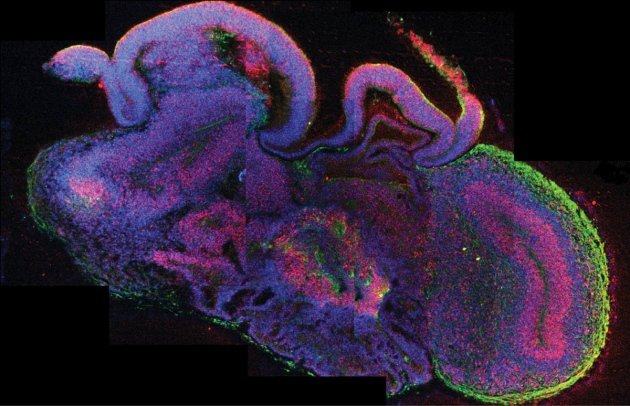

Giza zelula ametan oinarrita, garun txikien antzeko egiturak (organoideak) sortu eta funtzional mantentzea lortu dute Salk Institutuko (AEB) ikertzaileek. Zaila da organoideak in vitro bizirik mantentzea –hala geratu zen agerian duela bost urte lehenengo aldiz giza minigarunak sortu zituztenean–, hortaz, saguetan transplantatu dituzte, baskularizazioa garatu eta mantenugaiak eta oxigenoa eskura ditzaten. Arrakastatsua izan da esperimentua: 14 egunetan organoideek odol-basoen sare konplexua garatua zuten jada, eta beren neuronek saguen garunarekin konexioak sortu zituzten.

Guztira, 233 egun eman dituzte bizirik. Organoideak diferentziatzen eta heltzen joan dira hilabete horietan guztietan. Hildakoan, giza garunaren egitura eta heldutasun zelularra jaioberri batenak ziren.

Lehenengo aldia da giza garun organoideak beste espezie batean txertatzen direna, eta kezka etikoak ere ekarri ditu: saguen adimena aldatuko al da? Are gehiago, giza kontzientzia beste animalietan ezartzerik badago? Galdera asko eta erantzun gutxi, oraingoz. Salk Institutuan egindako transplantean saguek ez dute gaitasun berezirik erakutsi, Nature Biotechnology aldizkarian argitaratu dutenez. Ez dago argi zer gertatuko zen sagu helduetan egin beharrean sagu jaioberritan transplantatu izan balira.

Zalantzak zalantza, giza garun organoideak saguetan garatzeak asko erraztu dezake garunaren modelizazioak egin eta gaitzak aztertzea. Are gehiago, kalte neuronala duten pertsonen garunean giza neurona osasuntsuak transplantatzeko bidea ere erraztu lezake etorkizunean.